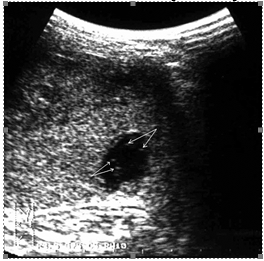

Прямым и наиболее постоянным (в течение острого периода травмы) эхографическим признаком подкапсульных разрывов селезенки с образованием внутриорганных гематом является наличие в паренхиме эхонегативной зоны (рис. 2, а, б). При гематомах, локализовавшихся в области полюсов селезенки или по ее диафрагмальной поверхности, эхонегативная зона имеет серповидную форму, повторявшую контур органа (рис. 2, в).

Рис. 2. Эхограмма подкапсульного разрыва селезенки: а – внутриорганная гематома; б – линейные разрывы паренхимы; в – подкапсульная гематома.

Необходимо указать, что при первичном исследовании (3–5 часов после травмы) ни в одном наблюдении не представилось возможности достоверно выявить подкапсульный разрыв селезенки в виде эхонегативной зоны. Повреждения визуализировались как нечетко очерченные участки паренхимы с незначительно сниженной эхогенностью, имевшие «смазанную» структуру, нехарактерную для паренхимы селезенки (рис 3).

Рис. 3. Эхограмма подкапсульного разрыва селезенки (3–5 часов после травмы). Зона повреждения указана стрелками.